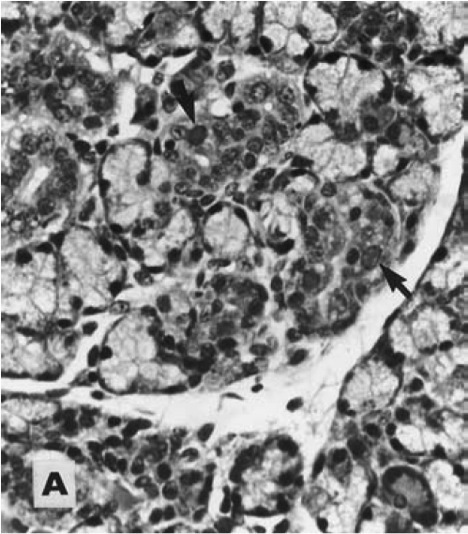

Mouse tissue. Etiology?

MAdV-2